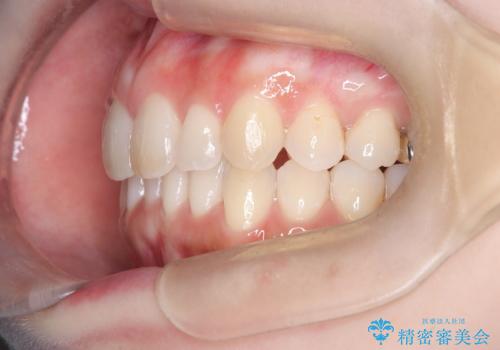

インビザラインで整えた前歯の歯並び

- 患者様は、上下前歯の歯列不正(ガタガタ)を主訴としてご来院されました。治療計画として、透明なマウスピース型矯正装置「インビザライン」を使用し、約2年の期間を見込んで前歯部の歯列を整える方針を立てました。特に下顎前歯に歯肉退縮のリスクがあるため、治療中にIPR(インタープロキシマルリダクション)を行い、歯間を適切に削ることで、過度な圧力を避け、歯肉退縮を防ぎながら配列を進めました。治療は慎重に進め、最終的にきれいで整った前歯の歯並びを目指しました。

インビザラインによる矯正治療は、患者様自身が装着するマウスピース型の装置を使用するため、装着時間の徹底が重要です。特に、下顎前歯の歯肉退縮を避けるため、IPRを施すことで歯間スペースを確保し、歯肉にかかる負担を減らしました。この方法により、歯並びを整えながらも歯肉の健康を保つことができます。治療期間中は定期的にチェックを行い、歯肉の状態や歯の動きを慎重に確認しました。また、治療後はリテーナーを装着して歯並びを維持し、安定させました。